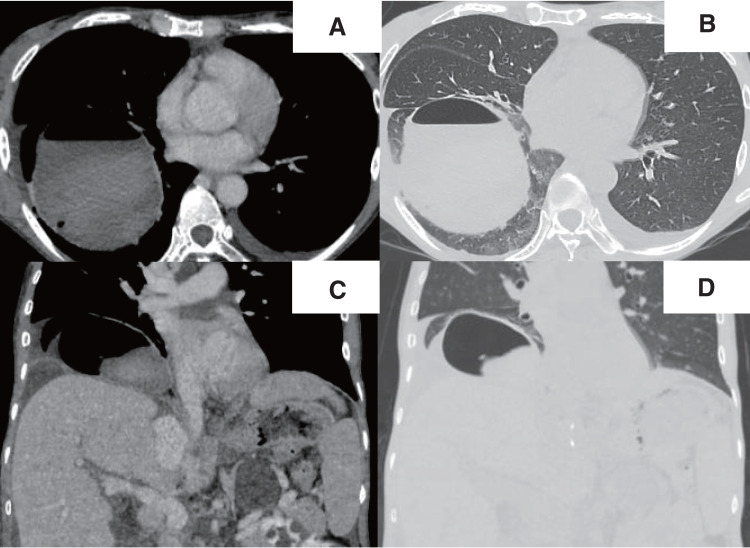

Case presentation: A 57-year-old woman with a diagnosis of autosomal dominant polycystic kidney disease underwent deceased-donor liver transplantation for polycystic liver disease. She did not have any background lung disease, although her right lower lobe was mostly atelectatic due to a remarkably elevated diaphragm. The liver transplant itself was uneventful. A small hole was made in the right diaphragm during the dissection of the liver, but it was successfully repaired without any injury to the lung. On postoperative day 1, the chest radiograph revealed a round hypertranslucency on the right side, which was initially considered subphrenic air retention, and no further evaluation was made at that time. Given that the hypertranslucency persisted, follow-up computed tomography was performed on postoperative day 18, and revealed an air-fluid level above the diaphragm in the right thoracic cavity. Thoracoscopic investigation revealed an intrathoracic hematoma within a pneumatocele in the right lower lobe, which was not detected in the pretransplant computed tomography. The hematoma was removed, and the pneumatocele was resected.